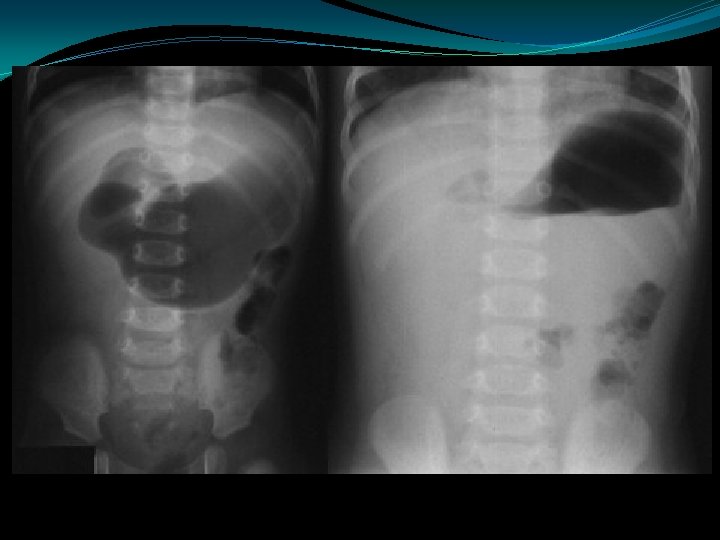

Hirschsprung’s Disease �Failure to pass meconium in 1 st 24 hrs �Absence of ganglion cells in mesenteric plexus �Most commonly rectosigmoid junction � 10% of cases involve entire colon � 10% of cases associated with Trisomy 21

Hirschsprung’s Disease �Contrast enema �Suction biopsy �Open biopsy �Rectal irrigation �Colostomy vs primary pull-through

Meconium Plug Syndrome �Present within the first 24 to 36 hours of age: �Abdominal distention �Vomiting (bilious) �Failure to pass meconium �Plain films show distal intestinal obstruction �Contrast enema usually shows: �distention of the right and transverse colon �transition near the splenic flexure to a narrow descending colon and rectosigmoid region �Meconium within the colon �Main differential diagnosis is Hirschsprung's disease: �In Hirschsprung's disease, aganglionic colon is usually normal caliber �In Meconium Plug Syndrome, colon is usually small